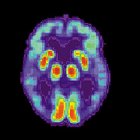

This is a PET scan of a brain affected by Alzheimer's disease. PET scans are used to show which brain cells are healthy and which cells are dead. In this picture, healthy cells are shown as green or red. The picture is courtesy of wikipedia.com.